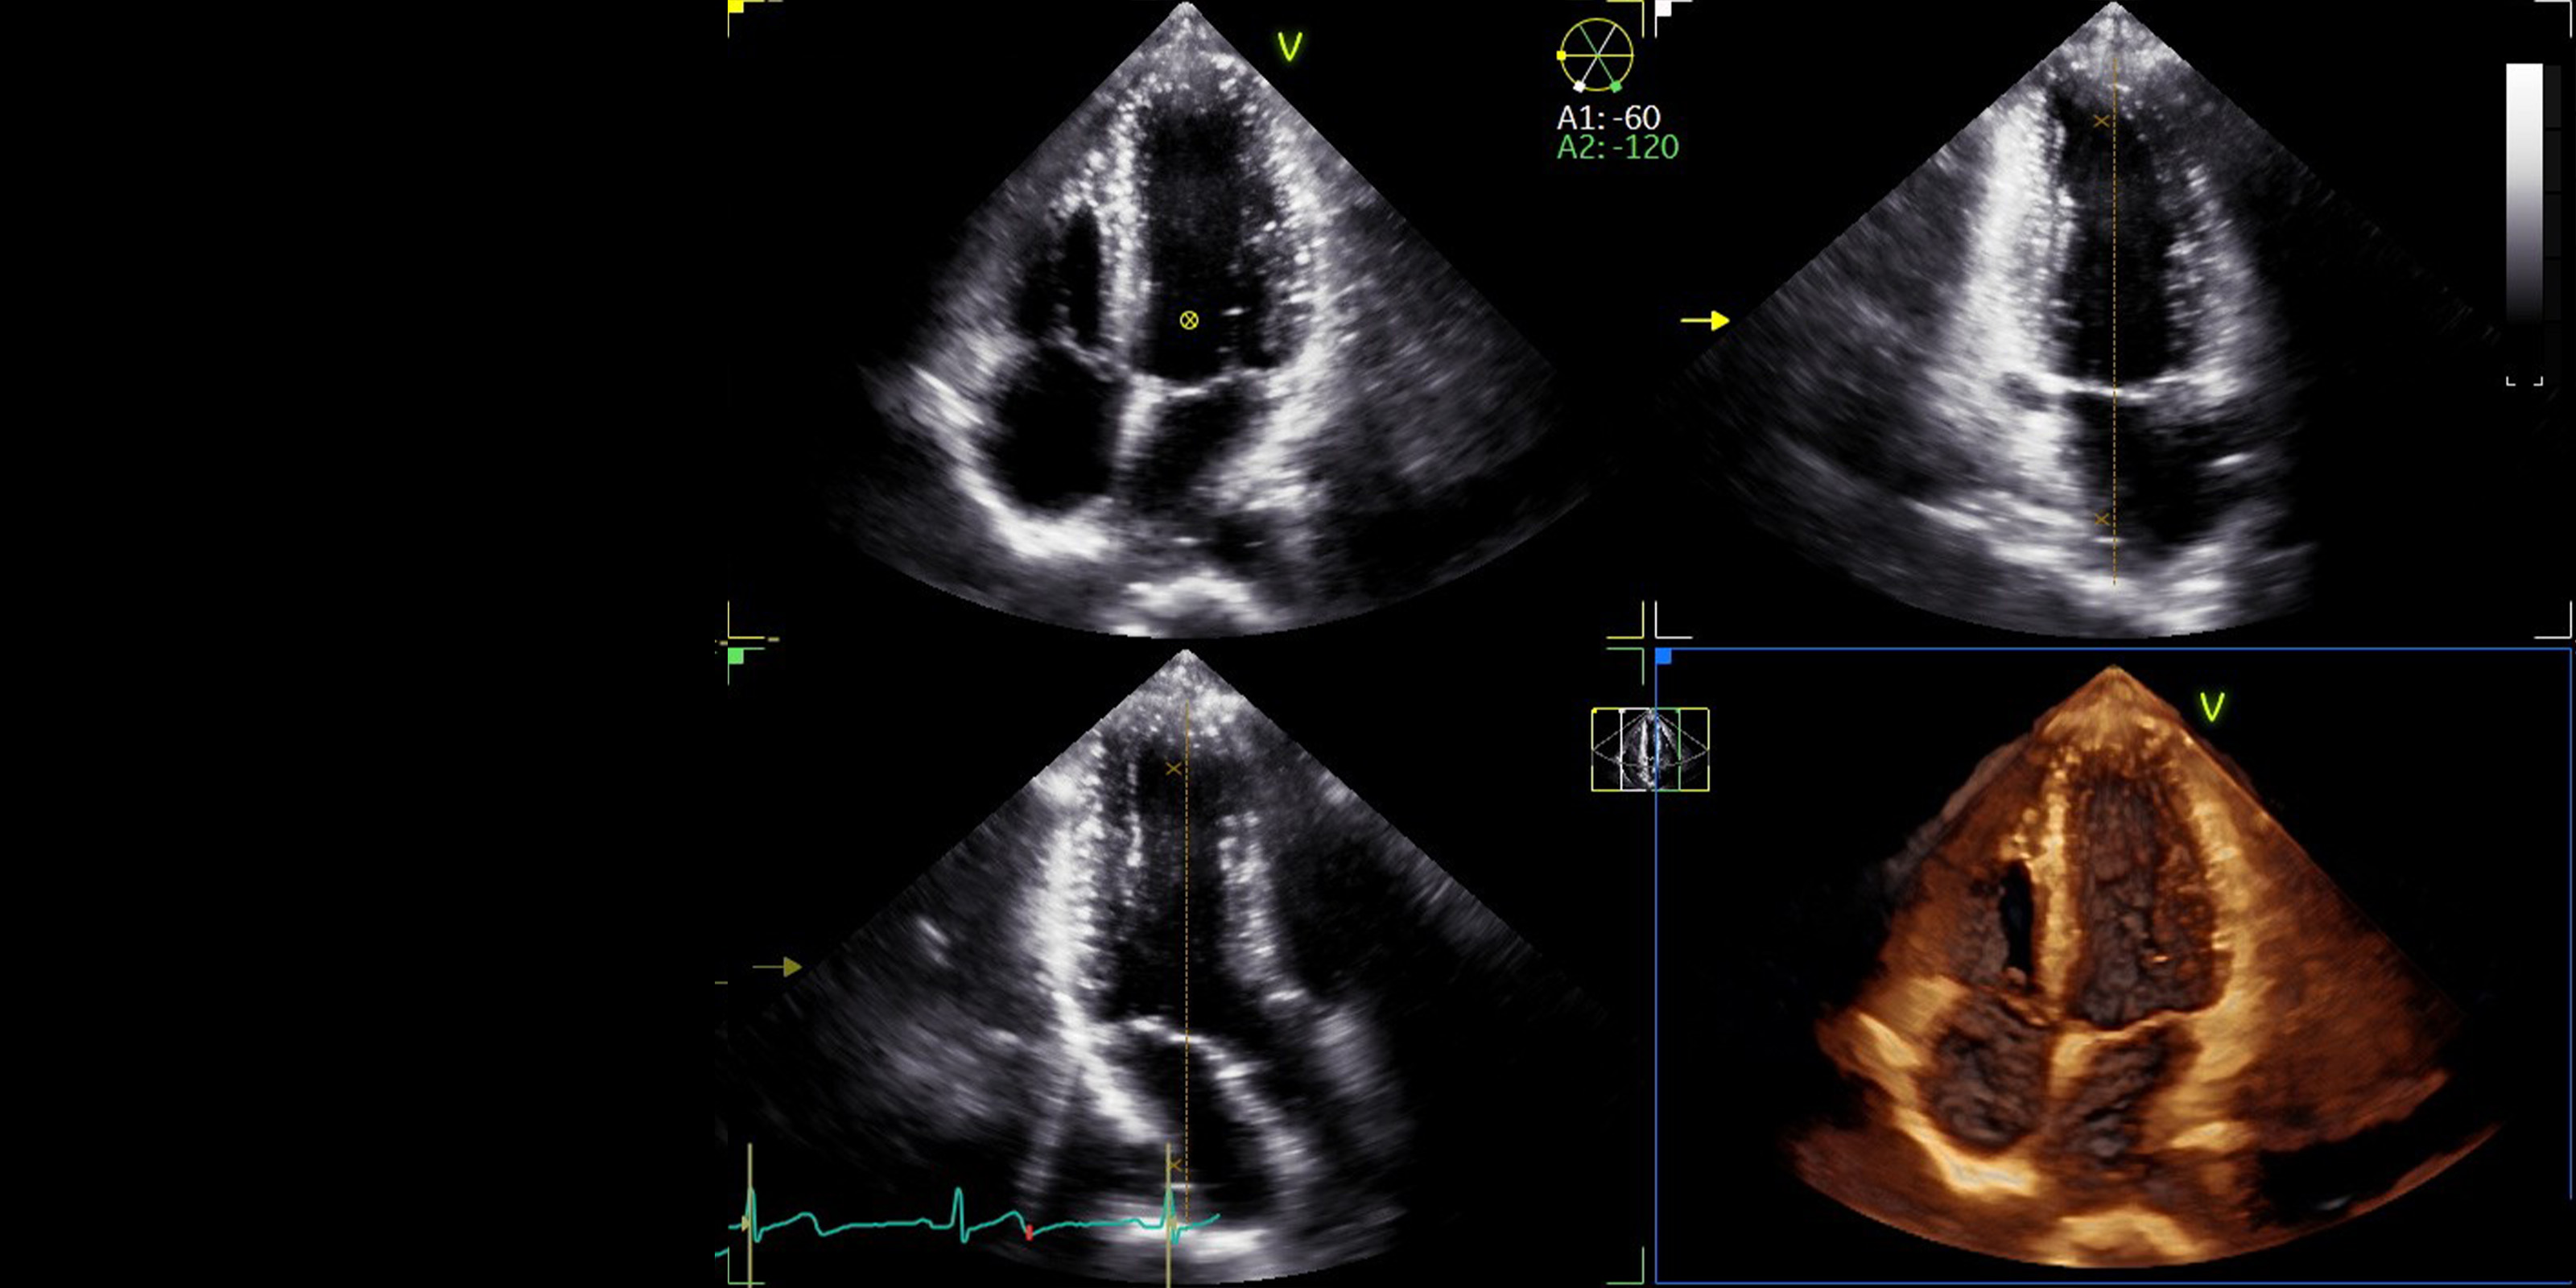

新たな診断の世界

UlPath(ウルパス)は「超音波を学びたい人」に開かれた、オンライン学習プラットフォームです。超音波技術の基礎から専門的な応用まで、段階的な学習プロセスに応じたコンテンツや、超音波医学の専門家として必要な知識・技能の習得を目指すためのコンテンツなど広く収載していきます。